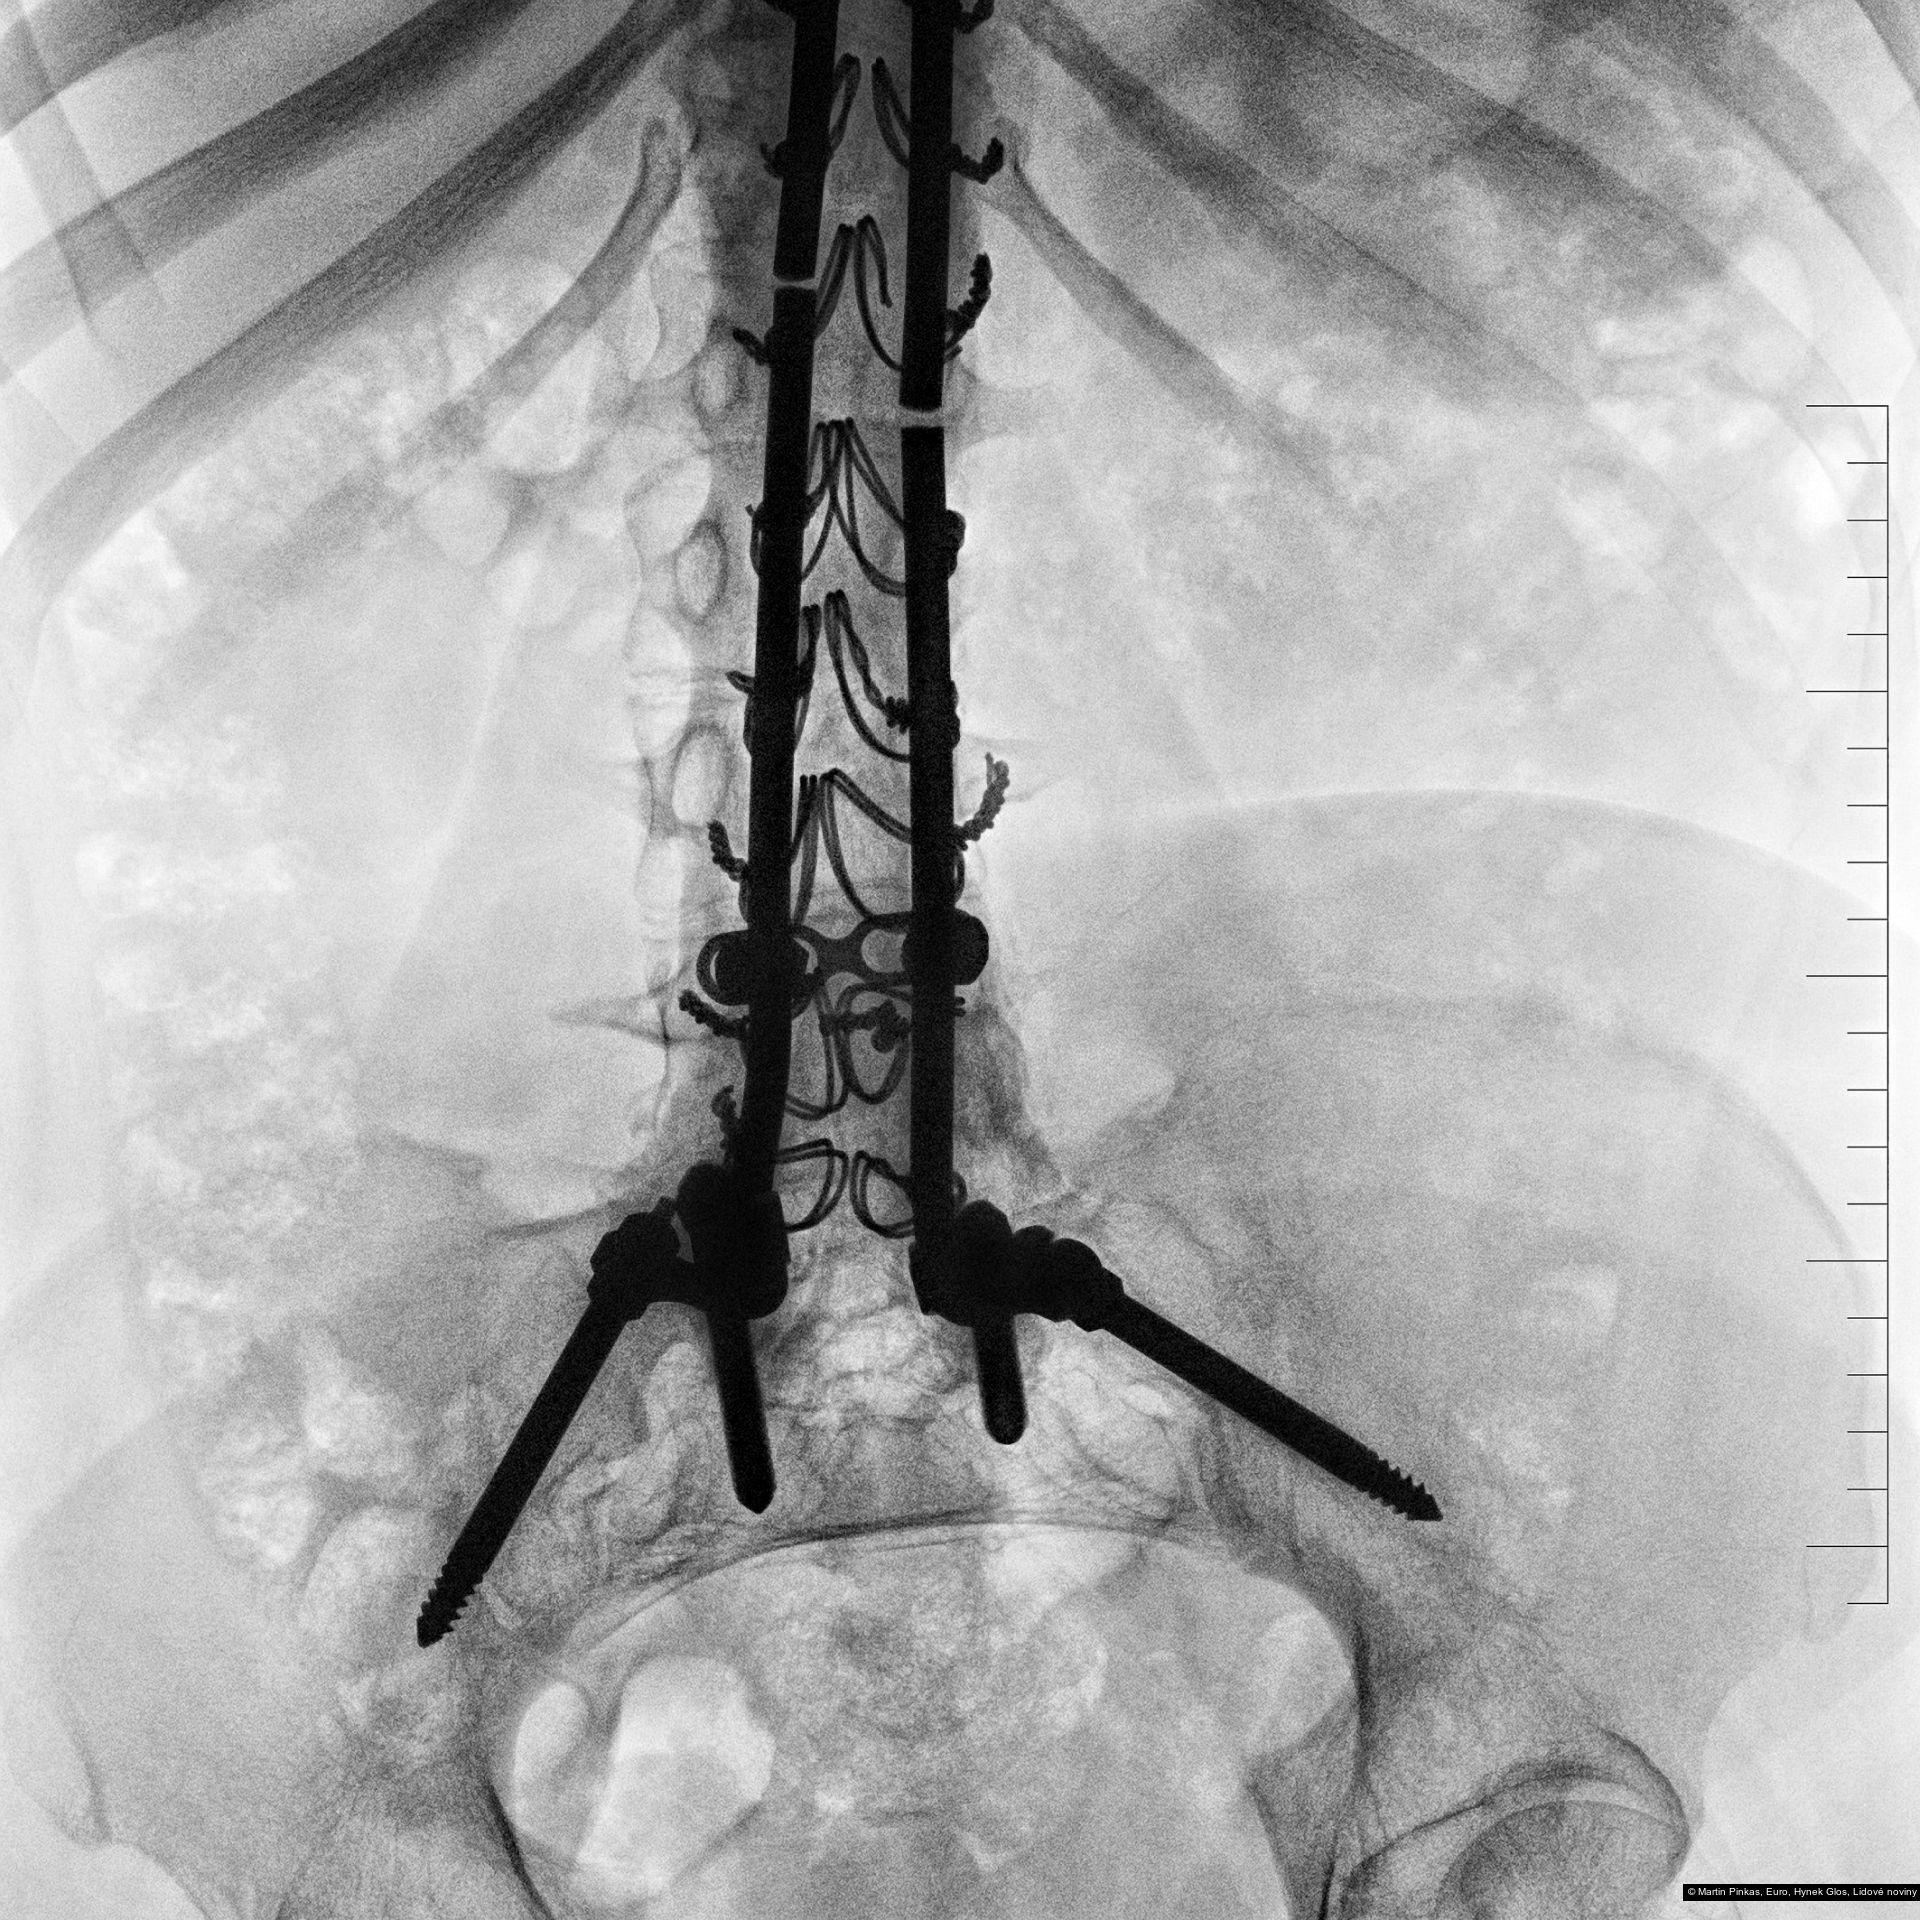

Příspěvek: X-portrait, nelékařské rentgenové portréty handicapovaných sportovců, Praha, Mostiště, 6.8. - 15.9.2010

Autor: Hynek Glos, Martin Pinkas

Příspěvek: X-portrait, nelékařské rentgenové portréty handicapovaných sportovců, Praha, Mostiště, 6.8. - 15.9.2010

Autor: Hynek Glos, Martin Pinkas

Příspěvek: X-portrait, nelékařské rentgenové portréty handicapovaných sportovců, Praha, Mostiště, 6.8. - 15.9.2010

Autor: Hynek Glos, Martin Pinkas

Příspěvek: X-portrait, nelékařské rentgenové portréty handicapovaných sportovců, Praha, Mostiště, 6.8. - 15.9.2010

Autor: Hynek Glos, Martin Pinkas

Příspěvek: X-portrait, nelékařské rentgenové portréty handicapovaných sportovců, Praha, Mostiště, 6.8. - 15.9.2010

Autor: Hynek Glos, Martin Pinkas

Příspěvek: X-portrait, nelékařské rentgenové portréty handicapovaných sportovců, Praha, Mostiště, 6.8. - 15.9.2010

Autor: Hynek Glos, Martin Pinkas

Příspěvek: X-portrait, nelékařské rentgenové portréty handicapovaných sportovců, Praha, Mostiště, 6.8. - 15.9.2010

Autor: Hynek Glos, Martin Pinkas

Příspěvek: X-portrait, nelékařské rentgenové portréty handicapovaných sportovců, Praha, Mostiště, 6.8. - 15.9.2010

Autor: Hynek Glos, Martin Pinkas

Příspěvek: X-portrait, nelékařské rentgenové portréty handicapovaných sportovců, Praha, Mostiště, 6.8. - 15.9.2010

Autor: Hynek Glos, Martin Pinkas